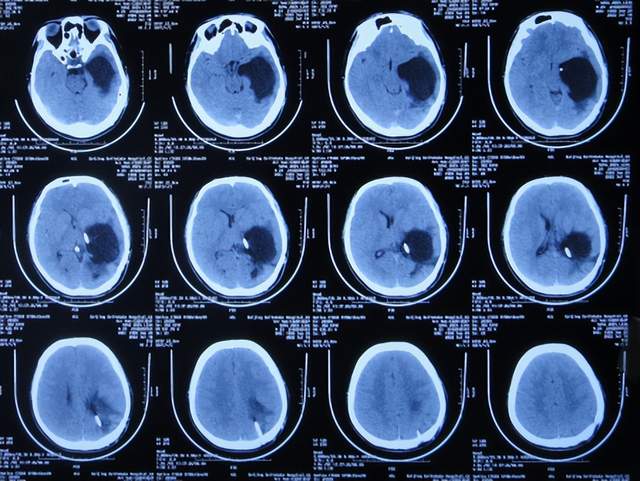

2021年3月26日(左颞角脑室腹壁外引流术后46天,脑脓肿切除术后19天),夹闭引流管1周左右,颞角没有扩张,因此进行了脑室腹壁外引流管拔除术。

但拔除引流管后11天即2021年4月6日,患者出现头痛,查头颅CT示颞角扩张(图-24)。

图-24:2021年4月6日头颅CT

因此于2021年4月8日,进行了脑室腹腔分流术;术后身体一切正常(图-25)。

图-25:2021年4月9日

于2021年4月18日(治疗近3个月)出院,出院时:身体一切正常。

三、第2次在李小勇脑脊液科治疗过程和结果

出院后5个月即2021年9月中旬,出现偶尔头痛的症状,因此于出院后7个月后即2021年11月10日,第2次来到李小勇脑脊液科;入院时:时有头痛(图-26),身体其他正常;查头颅CT示左侧颞角扩张(图-27)。

图-26:2021年11月10日入院时

图-27:入院时头颅CT

入院后2天即2021年11月12日,给予了颞角分流管调整术;术后第2天查头颅CT示颞角仍扩张(图-28)。

图-28:2021年11月14日头颅CT

入院治疗14天即2021年11月24日,查头颅CT示颞角缩小(图-29),患者头痛基本消失(图-30)。

图-29:2021年11月24日头颅CT

图-30:2021年11月24日

2022年1月4日(李小勇脑脊液科第2次治疗55天)出院。出院时:头痛已消失1月余(图-31),身体一切正常,查头颅CT示未见异常(图-32)。

图-31:2022年1月4日出院时

图-32:出院时头颅CT

四、第3次在李小勇脑脊液科治疗过程和结果

第2次出院后5个月即2022年6月初,再次出现头痛的症状,因左侧颞角再次增大,于2022年7月18日,第3次来到李小勇脑脊液科治疗。入院时:仅时有头痛。查头颅CT示左侧颞角扩张(图-33)。

图-33:2022年7月18日头颅CT

入院后3天即2022年7月21日,显微镜下颞角脉络丛切除术+分流管调整术,留置引流一根;术后查头颅CT示脑室内有2根管(图-34)。

图-34:2022年7月21日头颅CT

入院后11天即2022年7月29日(脉络丛切除术后8天),查头颅CT示引流术后状态(图-35)。

图-35:2022年7月29日头颅CT

入院治疗12天即2022年7月30日(脉络丛切除术后9天),给予拔除了原脑室腹腔分流管,查头颅CT示脑室内有一根管(图-36)。

图-36:2022年7月30日头颅CT